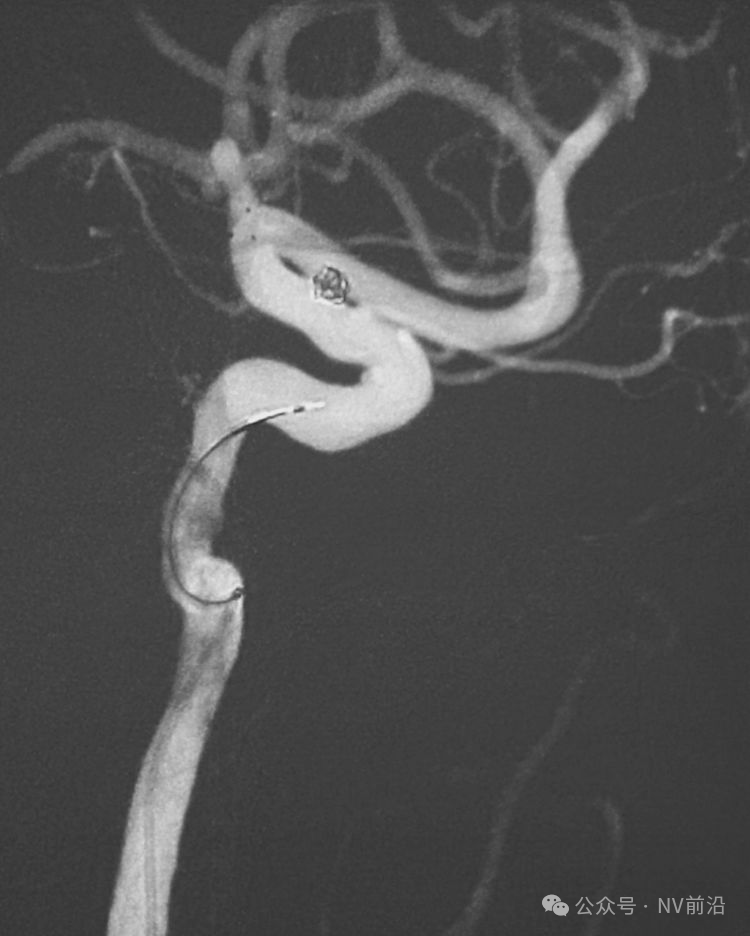

跨瘤颈释放Solitaire 4×20支架(蓝线),压住微导管(红线),在支架保护下经返折的微导管送入弹簧圈填塞瘤腔。

依次送入QC-2-4-3D,2-3-Helix,1.5-2-Helix,1.5-2-Helix四枚弹簧圈,最后一枚弹簧圈将管头(箭头)顶出瘤腔。

将Traxcess 14微导丝送入微导管,稍向远心端送微导管,使管头远离动脉瘤,再缓慢撤离。

解脱第一枚Solitaire 4×20支架后,套叠置入第二枚Solitaire 4×20支架,置入两枚支架的原因是考虑该瘤是夹层动脉瘤,多支架能够强化血流导向作用,有利于夹层愈合。

术后右椎动脉工作位造影,

以及正位造影显示动脉瘤完全栓塞,载瘤动脉畅通。